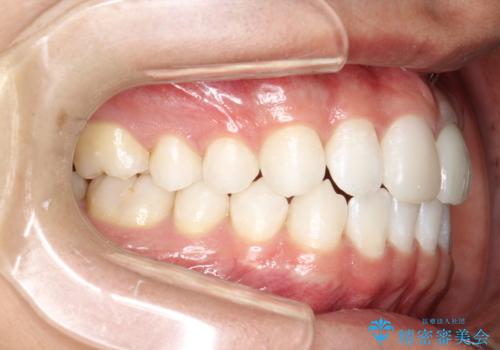

インビザラインによる矯正治療(非抜歯) 下の前歯の歯並びの改善

- 主に下の歯並びの改善を主訴としてご来院されました。

右下の犬歯と前歯が大幅に重なっているのと、歯の向きも大きく横に倒れています。この部位の正常な配列のためには、3次元的に大幅な移動が必要となりました。

インビザラインの特色を生かした歯牙移動計画を作成し、非抜歯にて治療を行いました。

概ね1年弱で治療が完了しました。

前歯の大きな3次元的移動を可能にするために、当院独自の工夫を随所に盛り込み、狙い通りの治療結果を得られました。